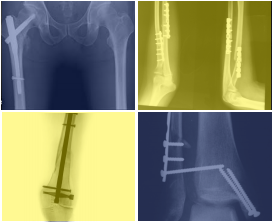

Centro Médico Teknon acull el I Curs d'Osteosíntesi per abordar les tècniques més novedoses de traumatologia...

Per primera vegada el Centro Médico Teknon - Grupo Quirónsalud acull el I Curs de Osteosíntesi "Actualització del tractament quirúrgic de les fractures". - 17 de marzo de 2016